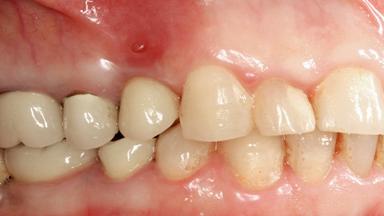

Biological complications caused by undetected cement residue have been receiving much attention. Excess cement might be responsible not only for rapidly developing of peri-implantitis, but also for delayed or chronic manifestations of the disease many years after cementation (Wilson 2009; Linkevicius and coworkers 2013). Invitro and clinical studies have shown that it is very difficult or even impossible to completely clean up excess cement at subgingival margins, so popular in cemented restorations (Agar and coworkers 1997; Linkevicius and coworkers 2011, 2012). Possible outcomes of biological complications due to excess cement range from temporary inflammation of the peri-implant soft tissues without any serious esthetic and functional consequences all the way to implant loss. This report describes a case of peri-implantitis caused by residual cement; as well as the management and quite unusual resolution of the complication. The patient presented in 2009 with a draining sinus tract, tenderness on chewing, and tissue contact above the implant-supported restoration. The implant had been restored approximately three years before.